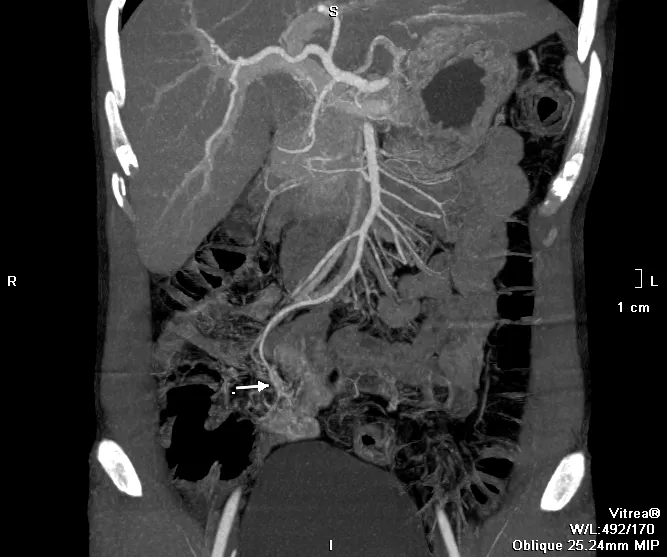

Hình ảnh CT của bệnh nhân khi vào viện cho thấy mạch máu dị dạng gây chảy máu. Ảnh: CO

Kết quả chụp CT cho thấy bệnh nhân có búi dị dạng mạch máu trong lòng ruột, đang có dấu hiệu chảy máu. Đây là thủ phạm gây chảy máu kéo dài. Bệnh nhân được hội chẩn, điều trị khẩn cấp bằng phương pháp can thiệp mạch để nút búi dị dạng. Sau thủ thuật 24 giờ, bệnh nhân không còn triệu chứng chảy máu, hồi phục và xuất viện.